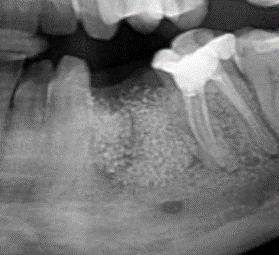

adbone®TCP is radiopaque, allowing the monitorization of the graft osteointegration.

adbone®TCP is intendend to be used as a bone void filler or augmentation material for bone defects that are not intrinsic to the stability of the bony structure:

Alveolar regeneration

Sinus lift augmentation: